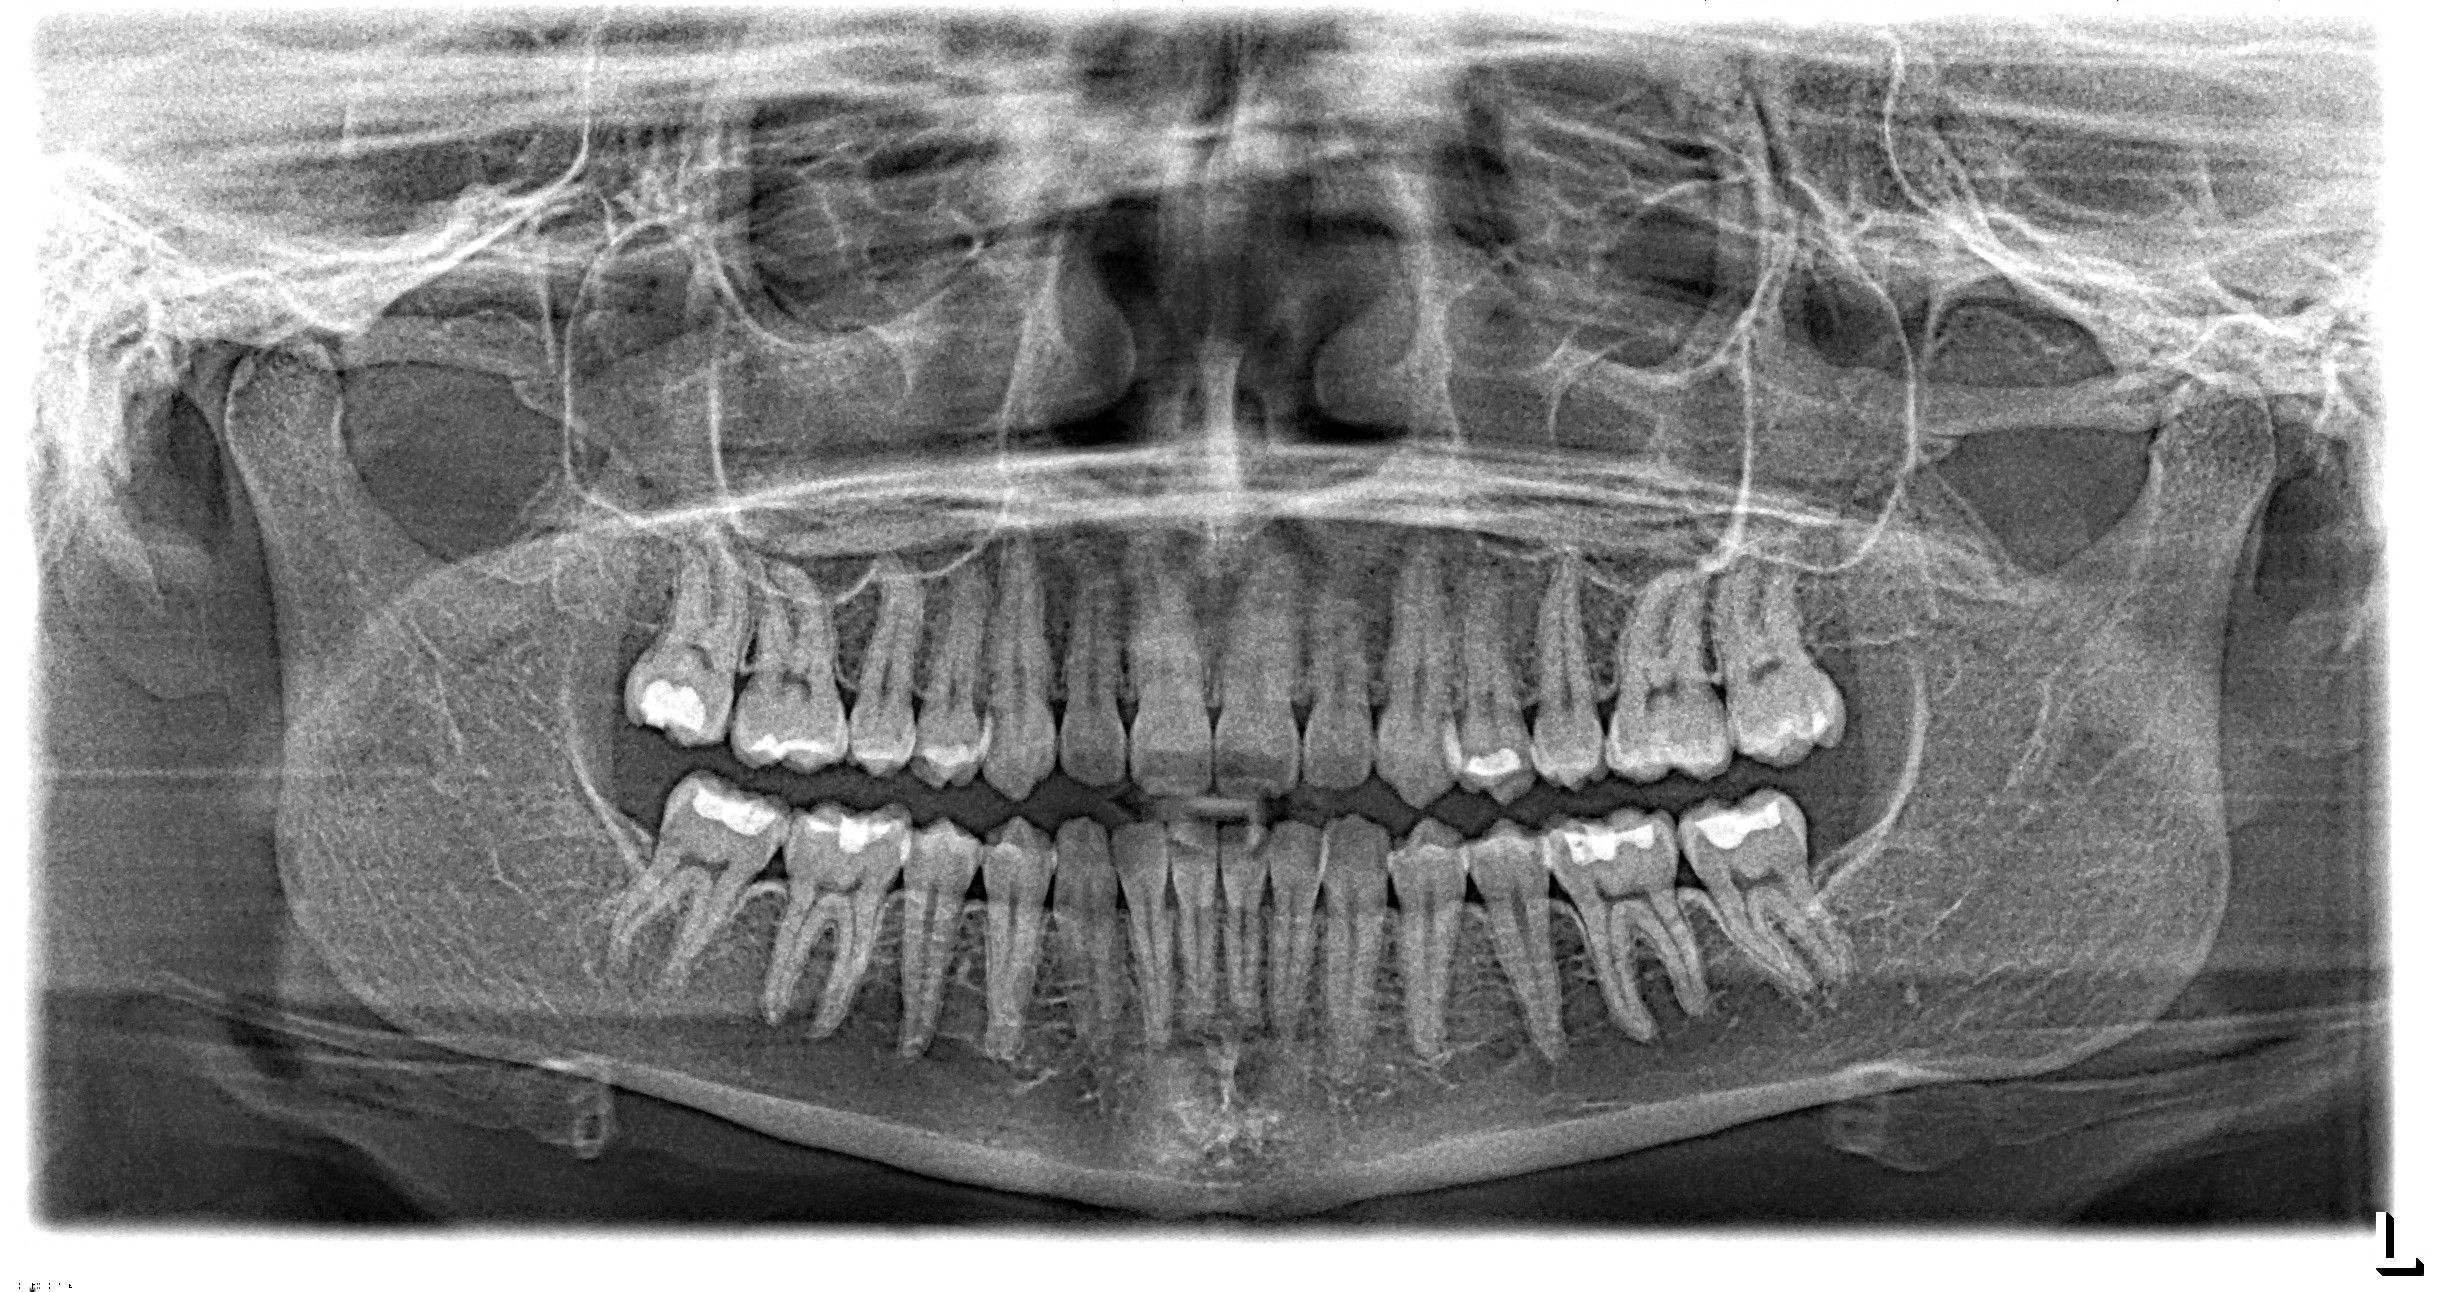

Healthy smiles start with seeing the whole picture. That is exactly what panoramic digital x-rays at Brady Dental Group in Amarillo, Texas provide. Instead of taking small, individual x-rays of just a few teeth, panoramic x-rays capture your entire mouth in one image. This gives the dentist a complete view of your teeth, gums, jaw, and surrounding bone structure.

The team at Brady Dental Group uses advanced digital imaging technology to make each visit more comfortable and efficient. Patients appreciate that the process is quick, safe, and informative. For many, panoramic digital x-rays are the first step toward understanding their oral health and planning the right treatment for lasting results.

Traditional x-rays only show small sections of your mouth at a time. Panoramic digital x-rays, however, use a rotating camera to create one large, high-quality image of your entire dental structure. This allows the dentist to see things that standard x-rays might miss, such as hidden cysts, jaw issues, or impacted teeth.

At Brady Dental Group in Amarillo, Texas, panoramic digital x-rays only take a few seconds and does not require film inside your mouth.

The detailed results help the dental team detect potential problems early and create personalized treatment plans. It is also an effective tool for monitoring changes over time, making it ideal for both new patients and long-term care.

When you arrive for your appointment, a friendly team member explains the x-ray process and positions you comfortably in the machine. The camera rotates around your head as you stand or sit still for about 10 to 20 seconds. The technology is digital, radiation exposure is minimal with no pain or pressure.

Once the image is captured, it appears instantly on the computer screen. This allows you to see exactly what the dentist sees, which helps make conversations about treatment options clear and easy to understand.

Panoramic digital x-rays at Brady Dental Group in Amarillo, Texas give a complete overview of your oral health, helping detect problems that may not show symptoms yet.

Dentists use panoramic images to examine the jaw joints, identify bone loss, locate impacted teeth, and even screen for oral cancers or cysts. For patients planning dental implants, orthodontics, or extractions, these x-rays provide essential information for accurate placement and safe treatment.

Because the image covers your entire mouth, dentists can spot patterns or connections between different areas, leading to better diagnoses and prevention. It is a proactive approach that supports long-term dental health and reduces the need for emergency visits.